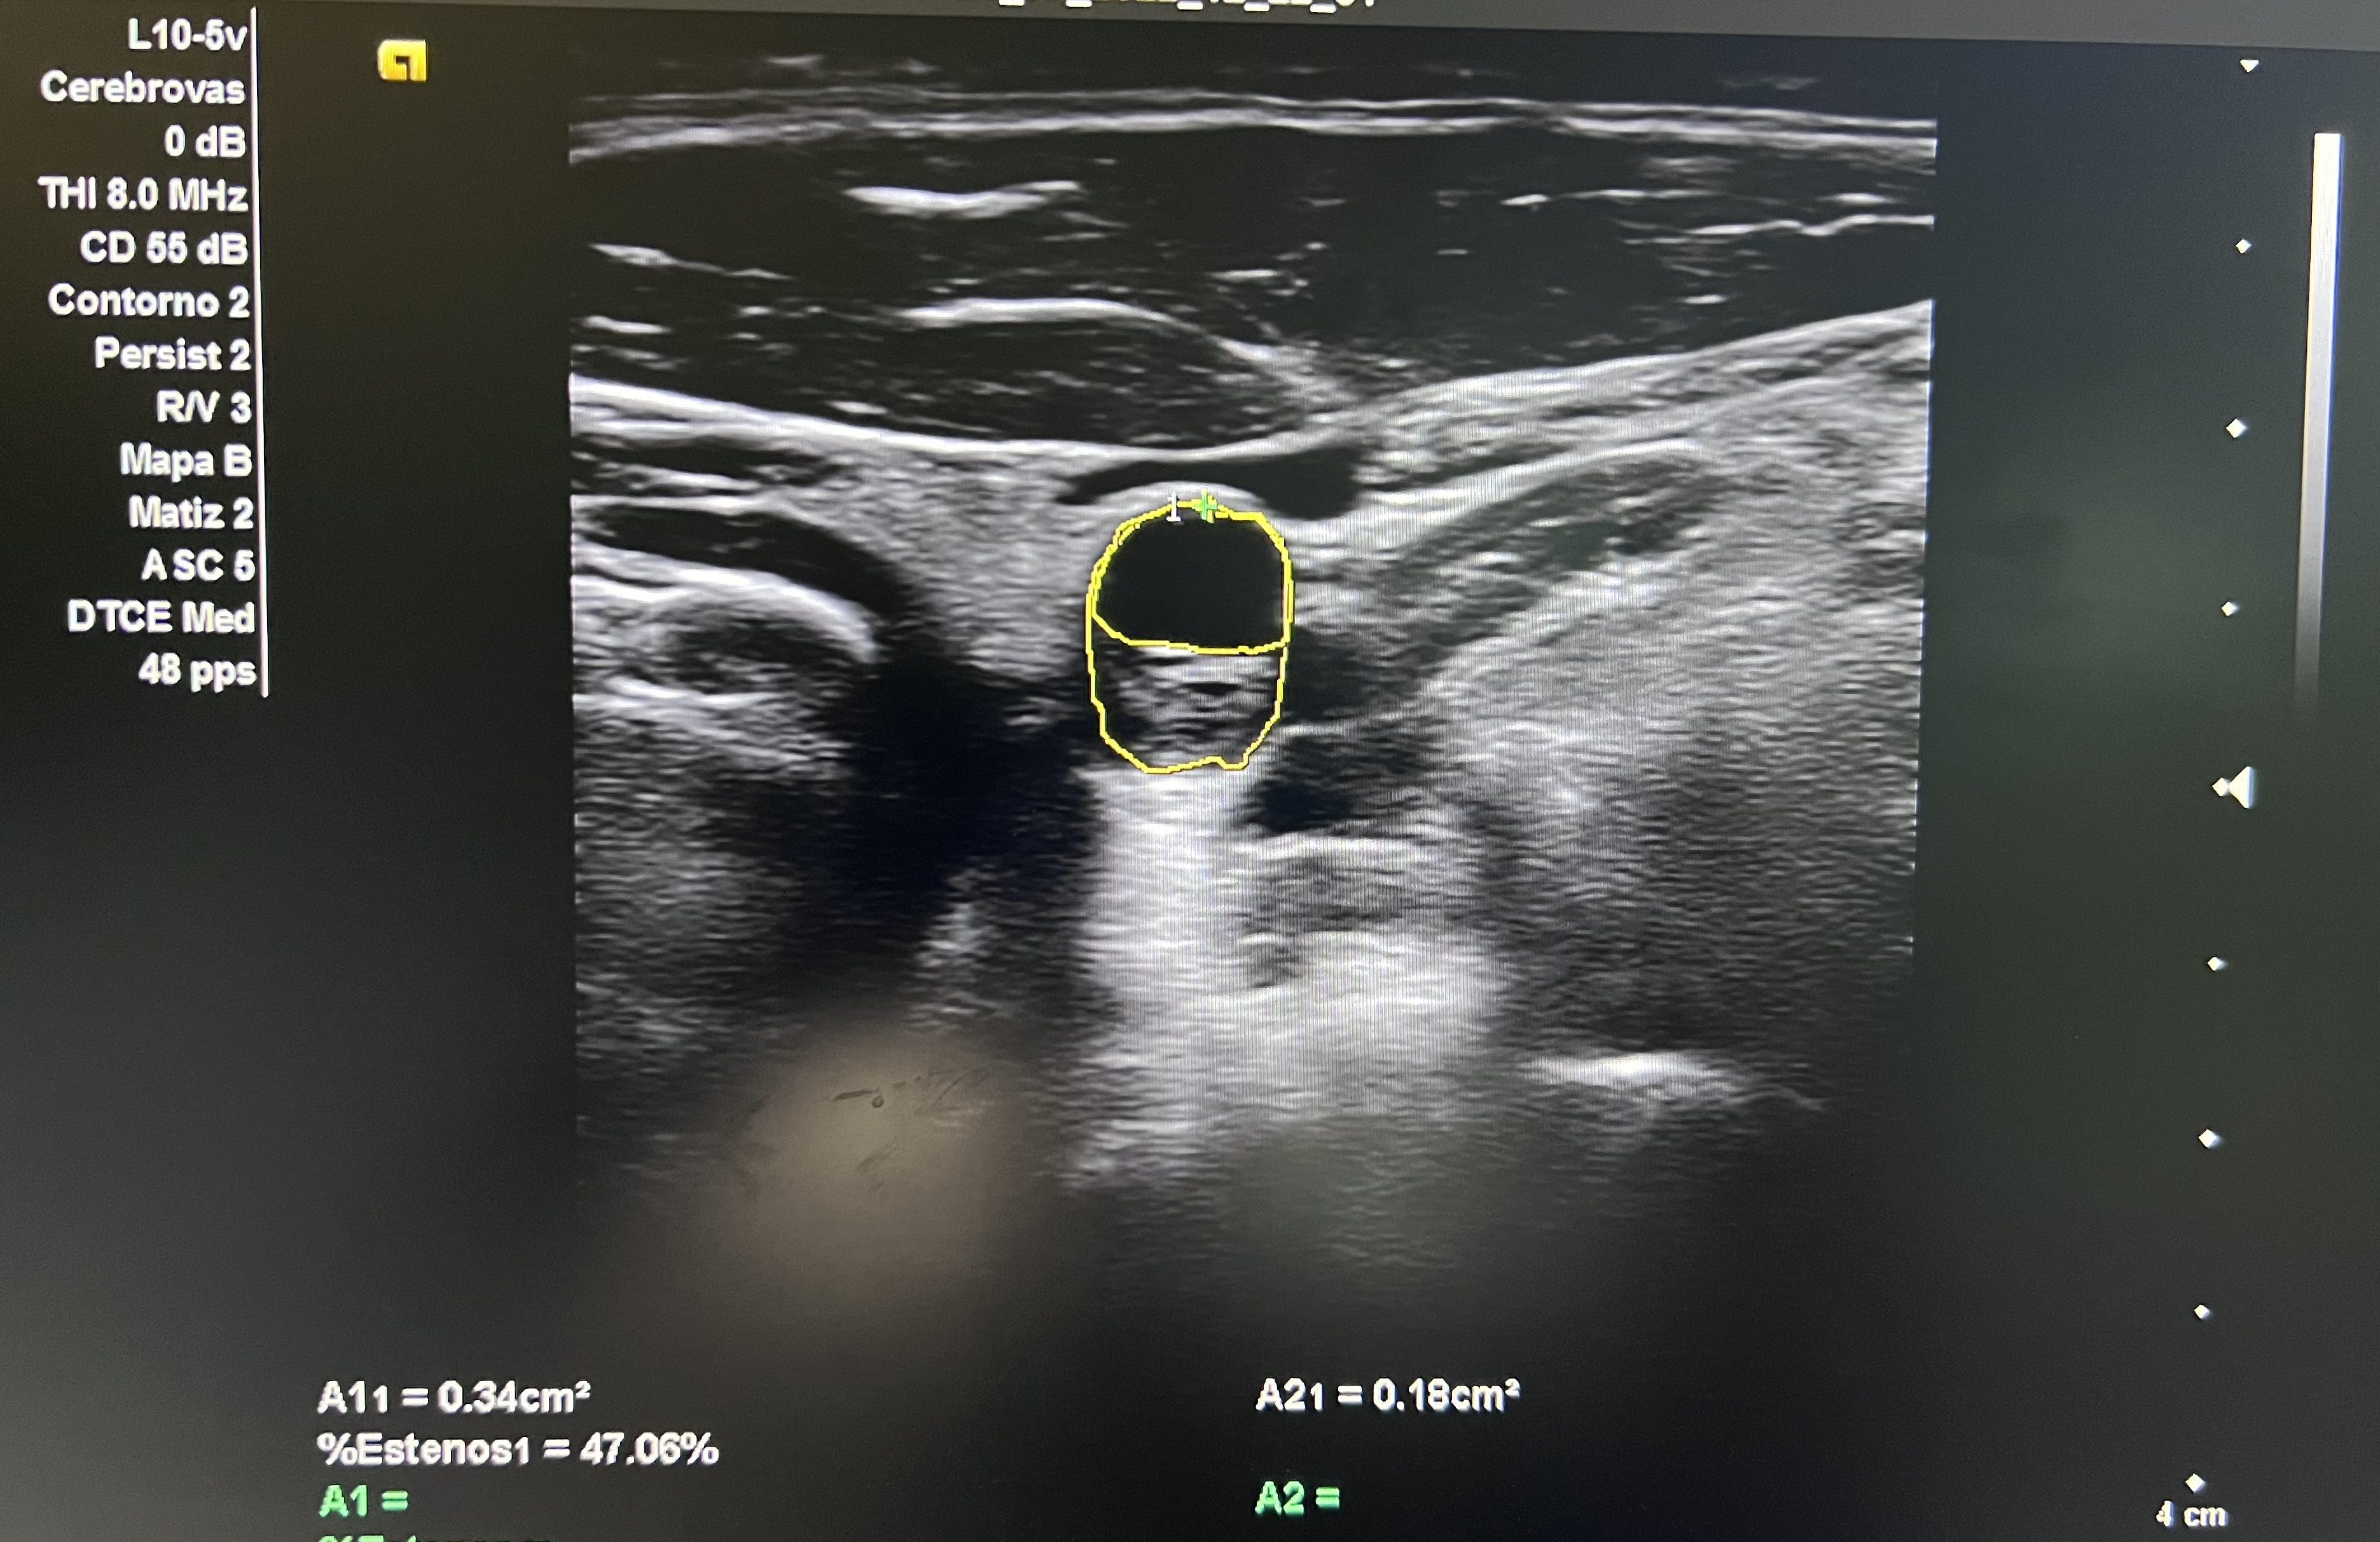

Aorta abdominal de calibre normal. Arteria carótida derecha sin lesiones. En arteria carótida común izquierda se observa placa longitudinal desde porción media hasta proximal que obstruye un 58% en su diámetro máximo.